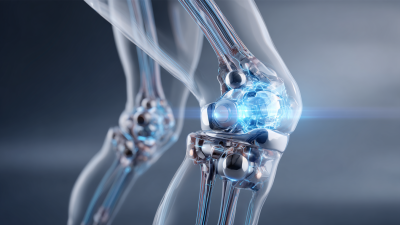

The Hip Arthrosis System comprises various components designed to enhance mobility for individuals suffering from osteoarthritis, particularly in the hip joint. This system includes custom-made orthotics that cater to abnormal walking patterns, which can result from joint degeneration. These orthotics not only provide support but can also help correct gait issues, thereby contributing to improved balance and reduced pain during movement.

Effective exercises and rehabilitation techniques play a crucial role in enhancing mobility, particularly for individuals dealing with hip arthrosis. Strengthening the muscles around the hip joint is essential for improving overall mobility and reducing pain. Engaging in targeted exercises helps support joint function and alleviates discomfort, enabling better movement. A combination of stretching and strengthening routines can significantly benefit those experiencing limitations due to hip issues.

Additionally, incorporating balance training into rehabilitation can enhance stability and prevent falls, a common concern among individuals with joint pain. Recent studies emphasize the importance of tailored exercise interventions, which not only improve mobility but also foster independence in daily activities. Simple mobility routines, such as dynamic stretches and strengthening exercises, can be seamlessly integrated into a daily regimen, ensuring continued improvement and engagement in physical activity, ultimately leading to a healthier, more active lifestyle.